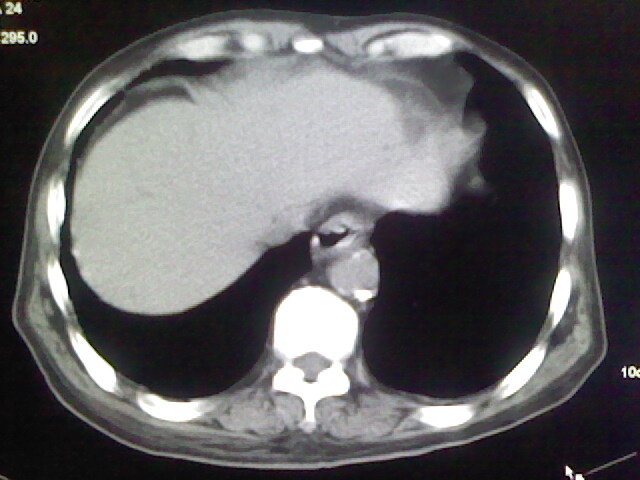

男,70岁,脑出血,长期卧床,左侧背部可触及肿块

肺部感染,背部筋膜增厚,考虑坠积性水肿或炎症

右侧肺部见片状密度增高影,边缘模糊。考虑炎症。另食管壁增厚。

食道里是什么

你放上去的